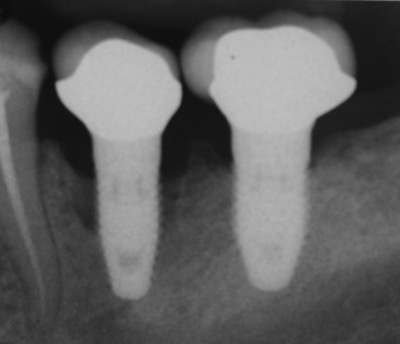

6️⃣ 植體鬆動(少見但最嚴重)

若植體本身與骨頭結合後受到過度咬力或感染,可能導致植體本體鬆動、斷裂。

這種情況通常需要重新評估、感染控制、甚至重新植牙。